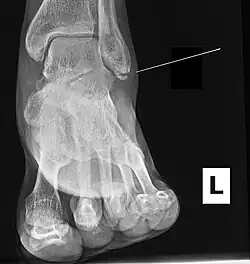

Ankle radiographs are used to detect widening of the tibiofibular syndesmosis or medial clear space. The medial clear space is the area between the talus of the ankle and the medial malleolus. Damage to the deltoid ligament and syndesmotic ligaments result in mortise instability, causing the talus to laterally shift and widen the medial clear space.[4][12] A clinical study, conducted in 2006 and published in the Journal of Bone and Joint Surgery, found that the medial clear space size of a normal ankle and an injured ankle measured at 4 millimetres and 5.4 millimetres in length respectively.[11] To confirm diagnosis, full-leg radiographs are used to inspect for fractures of the proximal fibula and widening of the interosseous clear space (or tibiofibular clear space). The interosseous clear space is the area between the medial side of the fibula and lateral side of the tibia. A peer-reviewed study, published in Injury in 2004, found that an interosseous clear space greater than 10 millimetres indicates diastasis of the syndesmotic ligaments.[4]

If necessary, computed tomography (CT) or magnetic resonance imaging (MRI) may also be used to clarify diagnosis. MRI scans can check for interosseous membrane or tibial tubercle damage if high instability of the ankle is diagnosed.[8][11] Arthroscopy may be used to diagnose a syndesmotic lesion but is often not recommended due to operative difficulty.[13] Stress radiographs of the ankle are used to assess the integrity of the deltoid ligament and tibiofibular syndesmosis.[9][13] The size of the medial clear space can also be measured using stress radiography.[11]